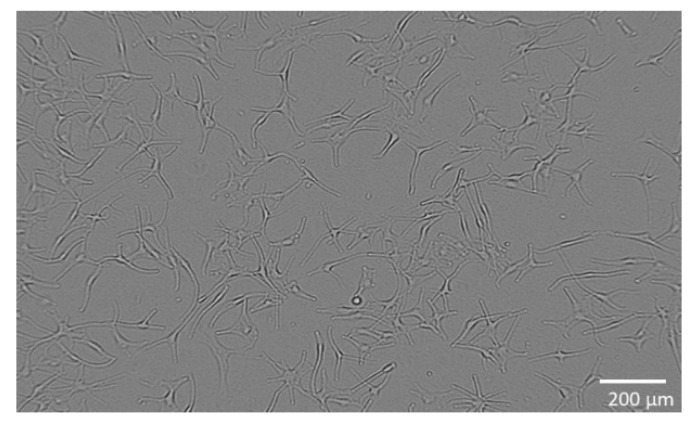

The combination of hemp and ginger extract has a promising inhibitory effect on melanoma cells [ref. 35]. Figure 1 shows the metabolic activity of WM-266-4 cells in the absence of extract and in the presence of extract at various concentrations (0.01–30.00 µg/mL). Treatment of WM-266-4 melanoma cells with hemp-ginger extract resulted in a significant decrease in metabolic activity in the presence of extract concentrations of 1.00 µg/mL and higher compared with the metabolic activity of melanoma cells in a medium without extract (control). The data were non-normally distributed and Levene’s test indicated equal variances (F = 0.995, p = 0.474). Therefore, the Kruskal-Wallis test was performed, which indicated a statistically significant difference in mean metabolic activity across concentrations (χ2 = 24.823, p = 0.003). The post hoc Dunn test confirmed significant differences between the mean metabolic activity of the control group (without extract) and the mean metabolic activity of the cells treated with extract of concentration 1.00 µg/mL and higher, as shown in Figure 1. The latter is also shown by the morphology of the cells in Figure 2. The images show the shape of the cells after application of the extract (1.00 µg/mL) (Figure 2b) and the shape of the cells in the control group (Figure 2a). Irregular cell shapes can be seen, indicating an apoptotic response.

The skin metastatic melanoma cell line WM-266-4 (ATCC® CRL1676™, Manassas, VA, USA) was purchased from American Type Culture Collection (ATCC, Manassas, VA, USA) and cultured in Eagle’s Minimum Essential Medium (EMEM, ATCC® 30-2003™, Manassas, VA, USA) containing 10 vol.% fetal bovine serum (FBS, ATCC® 30-2021™, Manassas, VA, USA) with addition of 0.02 vol.% MycoZap™ Plus-CL (Lonza, Portsmouth, NH, USA). The cells were incubated at 37 °C, 5% CO2, ≥90% RH and plated at a density of 2 × 104 viable cells per well in 96-well culture plates. The cells were cultured in a complete medium for 24 h to allow cell attachment (Figure 6). Normal human epidermal melanocytes (NHEM) (SI-104-05A, Taufkirchen, Germany) are primary cells and were grown in a complete medium: melanocyte growth medium (SI-135-500, Manassas, VA, USA). The cells were plated at a density of 1 × 104 viable cells per well in 96-well culture plates and cultured for 24 h in medium to allow cell attachment (Figure 7).

To analyse the metabolic activity of the cells, they were exposed to different concentrations of the extract (0.01–30.00 µg/mL) and incubated for 24 h, with five replicates performed. Control cells were not exposed to the extract but were cultured in the medium for the same time and under the same conditions. For cells’ metabolic activity measurement, a WST 8 Colorimetric Cell Viability Kit I (PromoKine, PromoCell, Heidelberg, Germany, EU) was used according to the manufacturer’s instructions. Absorbance (A) was measured spectrophotometrically at 570 nm (A570) (background A was measured at 630 nm (A630)) in pentaplicates for all samples. The percentage of the cells’ metabolic activity (MA) was calculated with the following equation:

where A represents the average value of absorbance calculated from five replicates. Additionally, cell morphology was observed with an inverted microscope (DM16000B, Leica) using a digital camera (DFC365 FX Leica, Lake City, IL, USA).